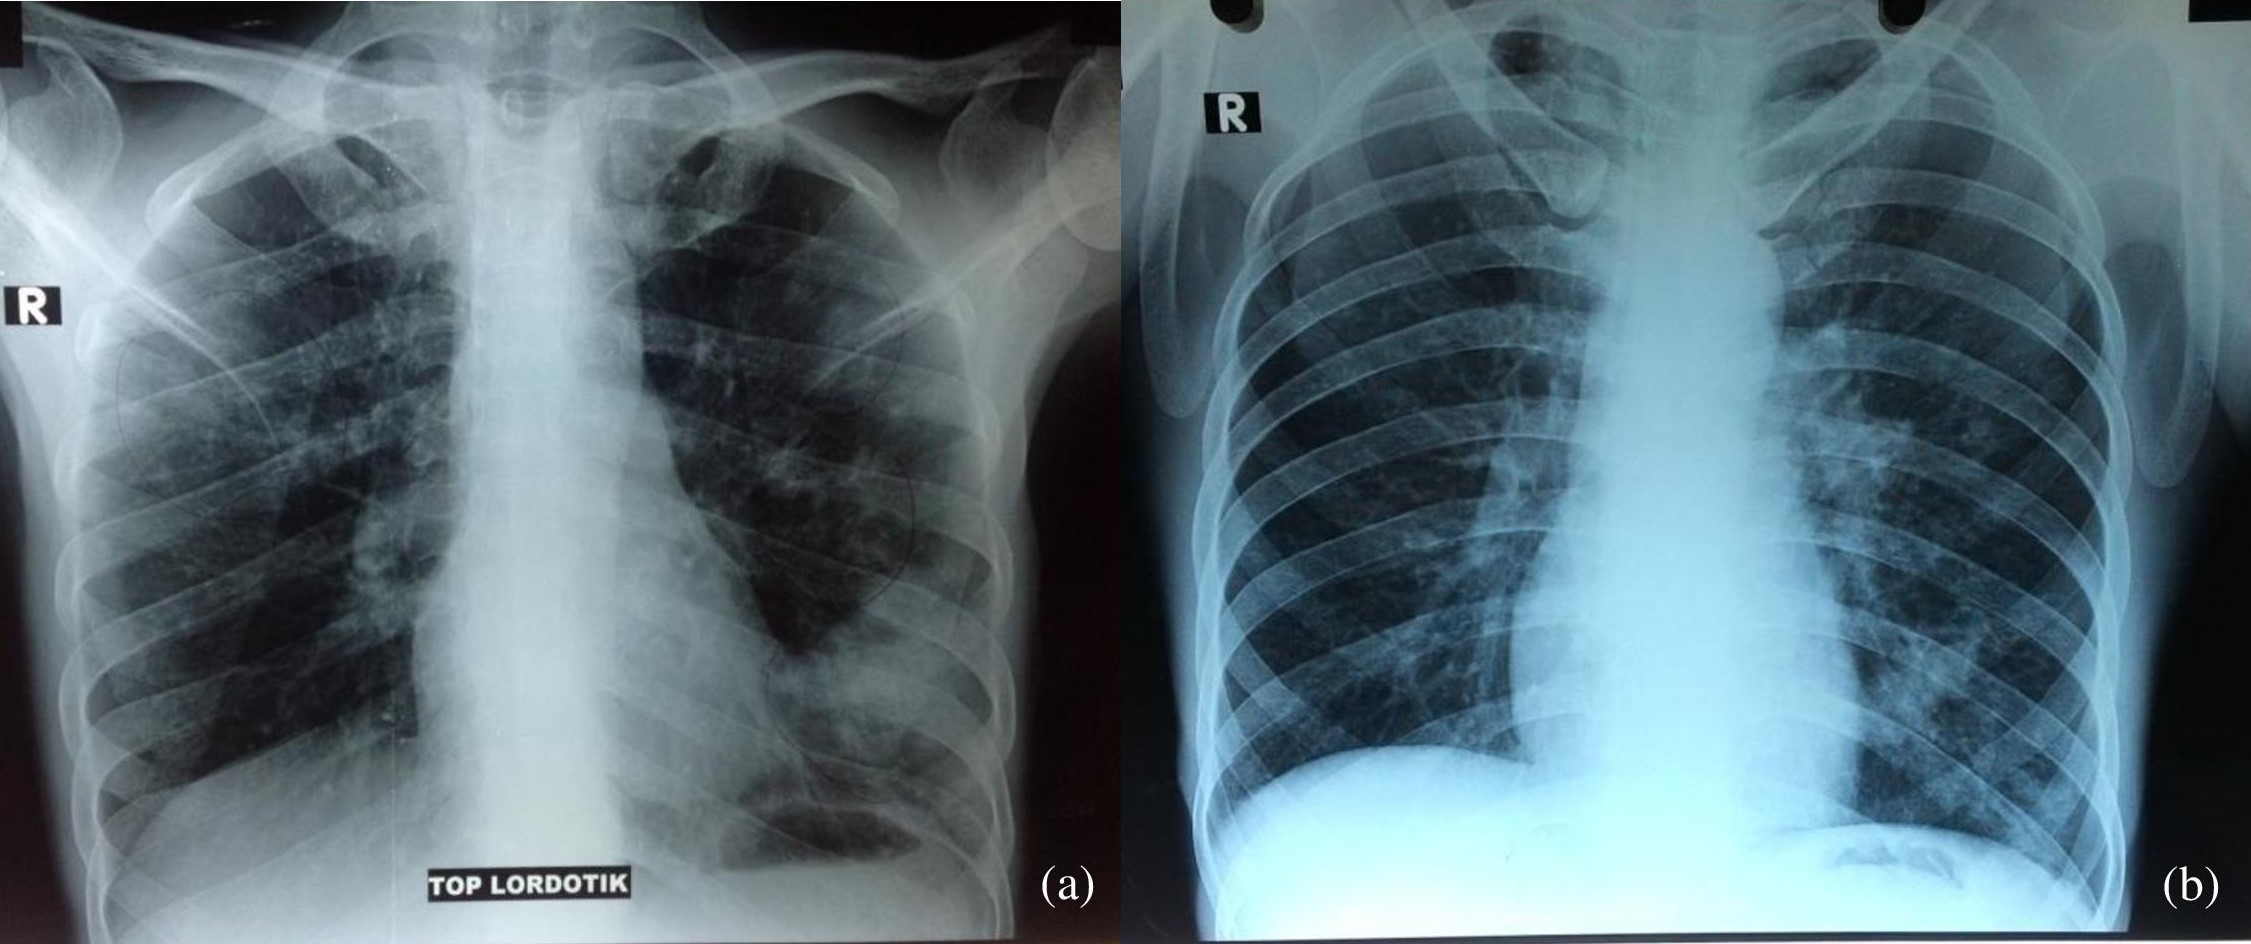

Ultrasonography of the neck revealed left perijugular lymphadenopathy. Plain chest and apicolordotic radiographs revealed moderate pulmonary TB (Figure 2). Urinalysis revealed albuminuria, pyuria, hematuria and bacteriuria (Table 1). Staining for acid-fast bacilli (AFB) was negative in sputum samples, and positive (+) for urine specimen. Urine culture showed no bacterial growth. Abdominal ultrasound revealed bilateral grade II to III hydronephrosis and chronic cystitis. This was consistent with subsequent findings in the intravenous urogram, which showed bilateral grade III hydroureteronephrosis due to obstruction at the distal ureters and contracted urinary bladder. However, histopathology result of urine cytology showed non specific chronic inflammation. Computerized tomography (CT) of the abdomen showed left adrenal gland hypoplasia, multiple cysts on the right adrenal gland, grade III to IV right hydronephrosis, grade II left hydronephrosis, chronic ureteritis and cystitis (Figure 3).

Click here to download Figure 2Figure 2. Chest radiographs. (a) apicolordotic view revealed fibrotic infiltrates and calcifications on the upper right and lower left lung fields. (b), improvement after 2 weeks of antituberculosis treatment.